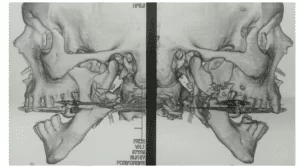

The clone was taken in the mouth to check the adaptation, with no need for adjustments. The assembly was then performed on the semi-adjustable articulator (ASA) (Bio-Art 4000-S, Brazil), for this it was heated to the stick godiva, which was inserted in the fork perforations, subsequent heating was performed and the fork carried in the mouth with the clone for the recording of the molar straps and incisal edges of the anterior teeth. Then, the facial arch was mounted by adjusting the fixation screws (figure 10). After obtaining the records, the base was made with heavy condensation silicone (Zetaplus®, Zhermack, Italy) and the upper orientation plane was mounted on the ASA (figure 11).

Figure 10: Facial arch assembly.

Figure 11: Top model mounted on the ASA.